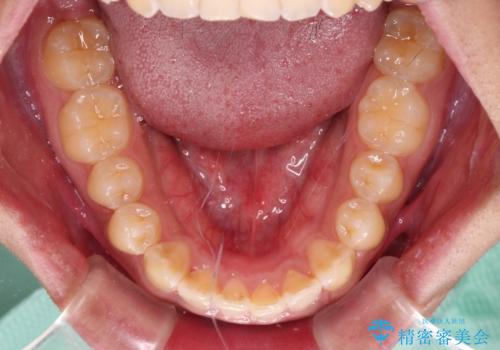

インビザラインによる上下歯列の側方拡大と後方移動、IPR(歯と歯の間を削る)にるスペースの獲得により、デコボコとディープバイトを改善することとしました。

気になっていたデコボコや隙間は改善し、きれいな歯列に整えることができました。

咬合力が非常に強い方であったため、これ以上のディープバイトの改善は困難となりました。